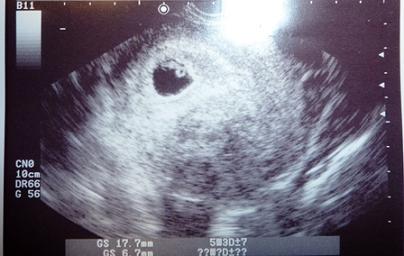

心音を確認した時の写真です(7w)。